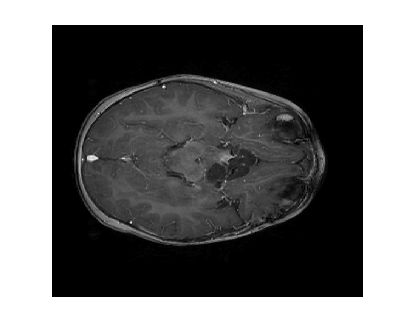

Figure 3 displays the reconstruction MSNR for the various test cases as cataloged in Table 1. Figures 1 and 2 display some examples of reconstructed images for cases of interest.

Due to its wide use in image processing, we consider the use of gradient sparsification with LACS-MRI. We show below that it is possible to produce image reconstructions with significantly higher Reconstruction SNR using gradient sparsification. We have repeated some of the simulations from above for different compression levels, , using the gradient transform to sparsify instead of the wavelet transform. We will refer to this as ”LACS-MRI with gradient sparsity.” We compared the performance of each sparsification method at each compression level using LACS-MRI and then compared this to the L1-W method. Again, we use a reference image and a follow-up image that we hope to recover as in Figure 8. We consider here only the phantom image, as it serves as a prime candidate for gradient sparsification, and is small enough that evaluation of all PDFs is computationally feasible.

Figure 12 shows the effect of a 2-fold scale difference on LACS-MRI image reconstructions. There are extensive streaking artifacts and significant detail is lost compared to the ground truth and the reconstruction using the modified method. Clearly, the Grayscale Compensation for Reference Based MRI Algorithm (GSC) can reduce these artifacts and help improve the visibility of structure.